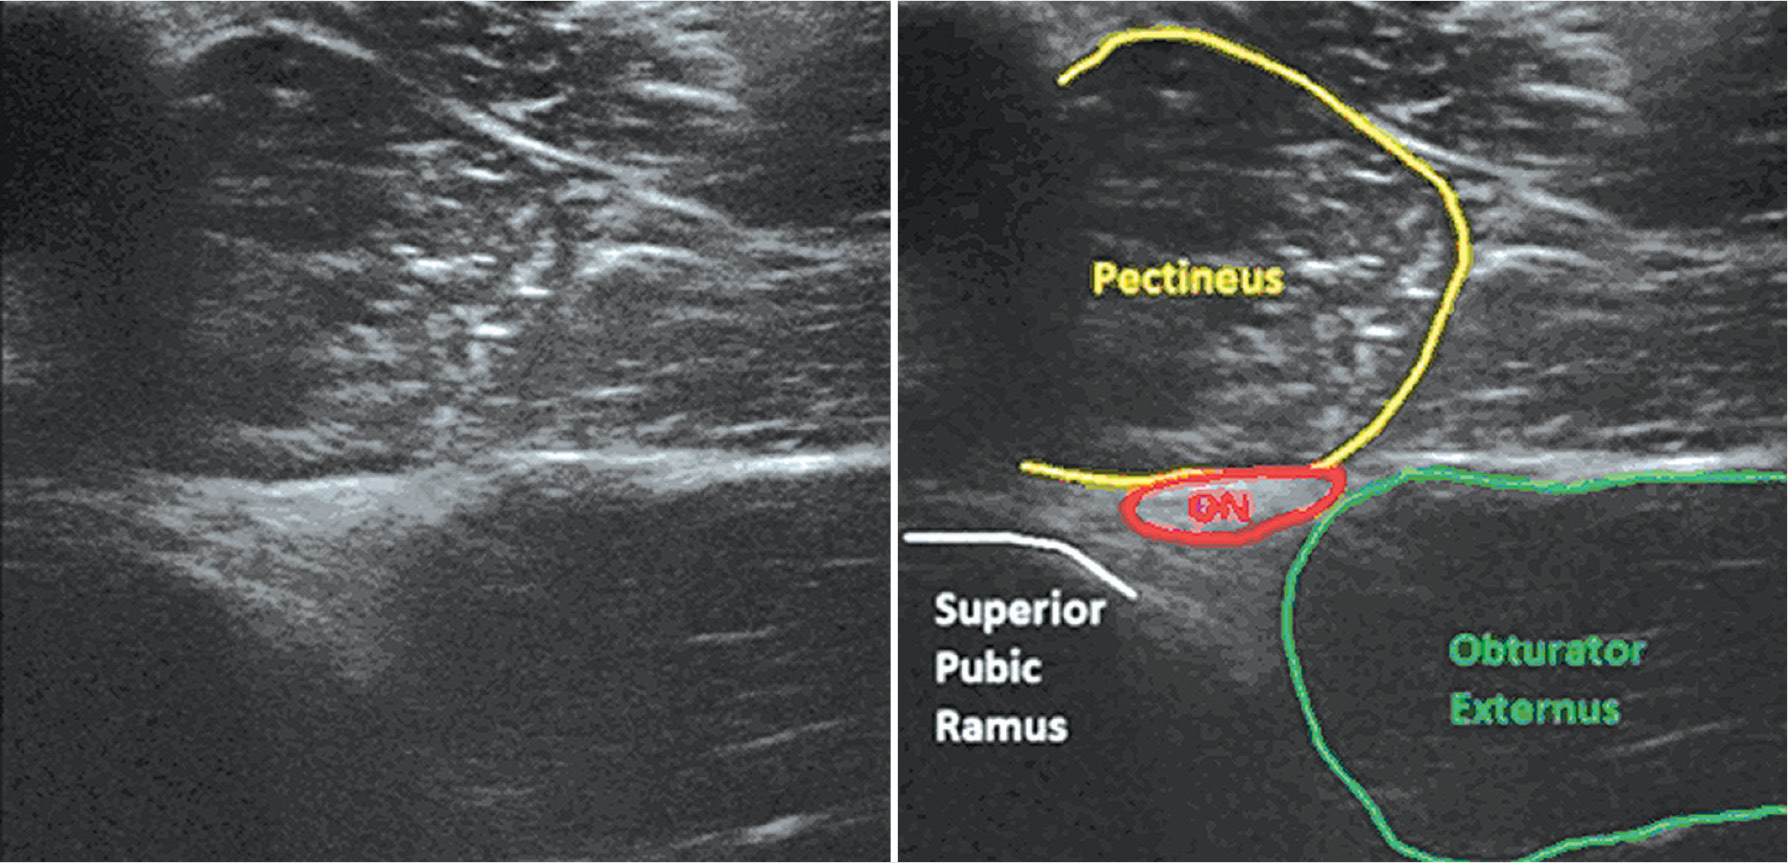

Положение пациента аналогично дистальному доступу. Датчик устанавливают параллельно паховой складке (рис. 5), визуализируют группу приводящих мышц, после чего наклоняют датчик краниально до тех пор, пока появится нижний край верхней ветви лобковой ветви (рис. 6).

Рис. 6. Проксимальный доступ к запирательному нерву по Lin [18]. ON — запирательный нерв

Fig. 6. Proximal approach to the obturator nerve block as described by Lin [18]. ON — obturator nerve

Латеральнее верхней ветви лобковой кости видны гребенчатая и наружная запирательная мышцы. Примечательно, что верхняя ветвь лобковой кости часто совпадает с межфасциальной плоскостью между более поверхностной гребенчатой мышцей и внешней запирательной мышцей. Иглу in plane вводят латерально к медиальному направлению. Иногда запирательный нерв (гиперэхогенная тень) может быть визуализирован сразу. Несмотря на то что запирательный нерв может разделяться проксимальнее этого уровня, а задняя ветвь может проходить через наружную запирательную мышцу [26], введëнный раствор местного анестетика распространяется проксимально и блокирует обе ветви запирательного нерва [29]. При отсутствии визуализации нерва можно ввести 3–4 мл изотонического раствора хлорида натрия, что позволит идентифицировать нервный ствол.